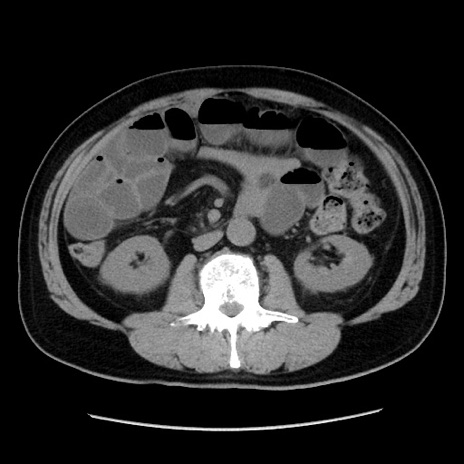

冠状断像